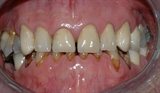

figur II

Slitasjen er spesielt tydelig i overkjeven.

Et detaljbilde viser rette, slitte kanter på tennene.